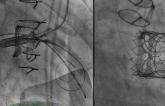

Less Paravalvular Leak With Newer Acurate neo2 TAVI: Registry

News Conference News TVT 2022

Surgical Explant or Redo for TAVI Failures? Some Registry Insights

More Support for Single Antiplatelet Therapy After TAVI

Subclinical Thrombosis After TAVI Benign, at Least to 3 Years

News Daily News